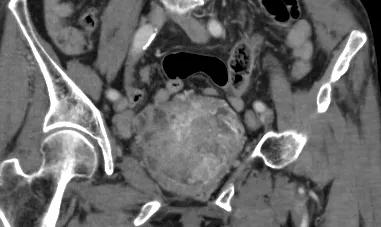

87岁的老太太,突然无诱因的下腹痛,伴血尿、血凝块,来我院治疗。经过CT增强检查发现膀胱巨大肿瘤。

CT结果见膀胱旁一巨大肿瘤